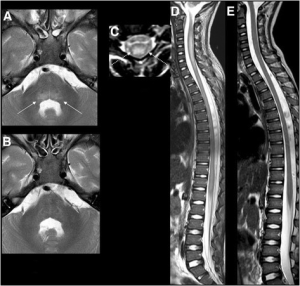

- MRI: spinal cord lesion, largely restricted to gray matter, spanning one or more spinal segments

- Spinal cord lesions may not be present on initial MRI if performed within the first 72 hours of onset of acute limb weakness.